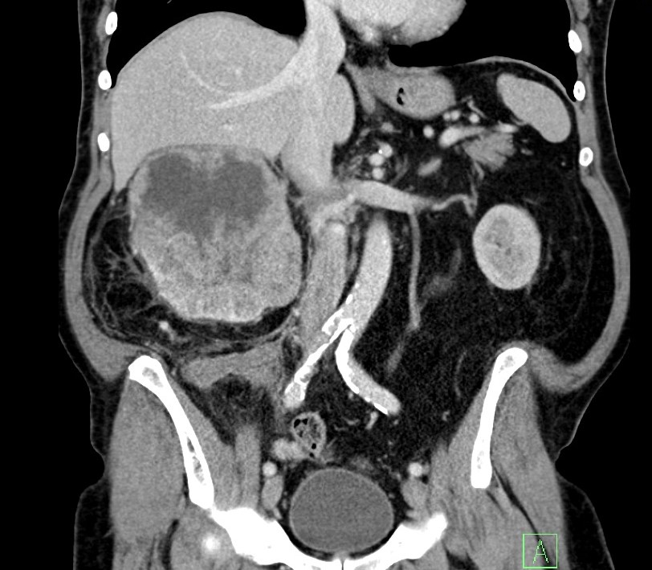

Do vaší ordinace vchází Milan Drahoš. Než se padesátiletý, velmi obézní muž dostane ode dveří k vámi nabízené židli, zadýchá se. Podle CT hrudníku, který si s sebou pacient přináší, má zvětšené uzliny v oblasti mediastina. Snímek odhaluje také mnohočetná ložiska plic. Není na co čekat, je třeba co nejrychleji zahájit léčbu. Ujmete se tohoto případu?